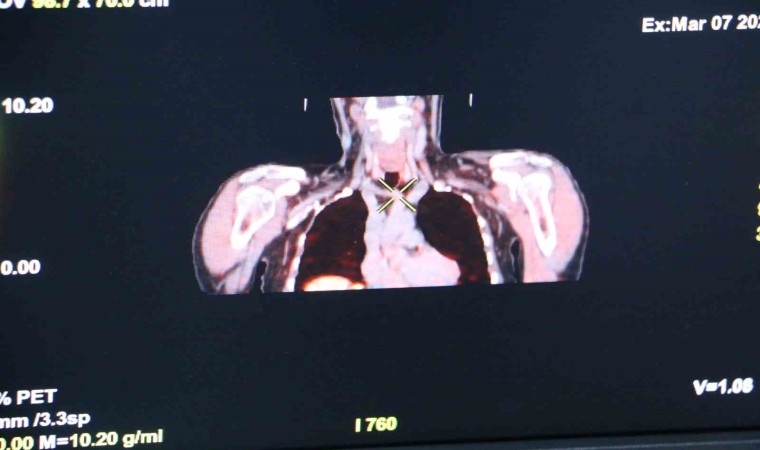

Hastanede Nükleer Tıp Uzmanı Doç. Dr. Halil Kömek ise, Kolin PET’in özellikle primer hiperparatiroidinde lokalizasyonunu saptayamadıkları vakalarda kullanılan bir görüntüleme yöntemi olduğunu söyledi. Doç. Dr. Kömek, “İlk olarak prostat kanserlerinde kullanılan bir görüntüleme yöntemi olan Kolin PET, tesadüf eseri boyun tutulmasıyla ve o bölgede paratiroid çıkmasıyla kullanılmaya başlandı. Sensitif ve spesifik değerleri oldukça yüksek, özellikle diğer yöntemlerle bulunamayan lezyonlarda yüksek saptama oranlarına sahip. Bu yöntemle enjeksiyondan 5 dakikadan itibaren görüntü alınabiliyor. Kolin PET, PET BT görüntülemelerinde kullanılan bir yöntem. 5’inci dakika ile 60’ıncı dakikadan sonra görüntüler alınarak daha önceden lokalizasyonunu saptayamadığımız paratiroid adenomlarının lokalizasyon saptamasında kullanılan bir yöntem” ifadelerine yer verdi.

Kolin PET’in Türkiye’de çok nadir merkezlerde yapılan bir görüntüleme yöntemi olduğunu dile getiren Kömek, “Hastanemizde geçen hafta itibarıyla 3 hastamızın görüntülemesini yaptık. Üçü de saptama aşamasında başarılı bir şekilde gerçekleşti. Bundan sonraki süreçte hastalarımız oldukça rutin uygulamamıza devam edeceğiz. Bölgemizde bu görüntülemenin olduğu başka merkez olmamakla beraber hastalarımızı en yakın Ankara’ya göndermek zorunda kalacaktık. Bu da onlar için zaman kaybı ve maliyetli olacaktı” dedi.